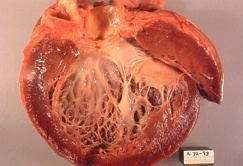

Es la prueba diagnóstica más valiosa y se ha de realizar siempre que se sospeche esta enfermedad.

Los hallazgos principales son los siguientes:

Otros hallazgos:

Los hallazgos principales son los siguientes:

- Hallazgo típico: dilatación de las cavidades afectadas y su forma esferoidal, especialmente del ventrículo izquierdo.

- Las paredes están adelgazadas.

- Disminución difusa de la función contráctil.

- Pese a que la fracción de eyección suele estar baja, el gasto cardíaco en estos pacientes puede ser normal. Esto se debe a que los volúmenes de eyección están muy aumentados y además existe una taquicardia compensadora.

Ecocardiografía 2D. Marcada dilatación de las cavidades cardíacas.

Ecocardiografía modo M. Severa dilatación de los diámetros diastólicos (dd) y sistólicos (ds) del ventrículo izquierdo (VI) con pobre contractilidad.